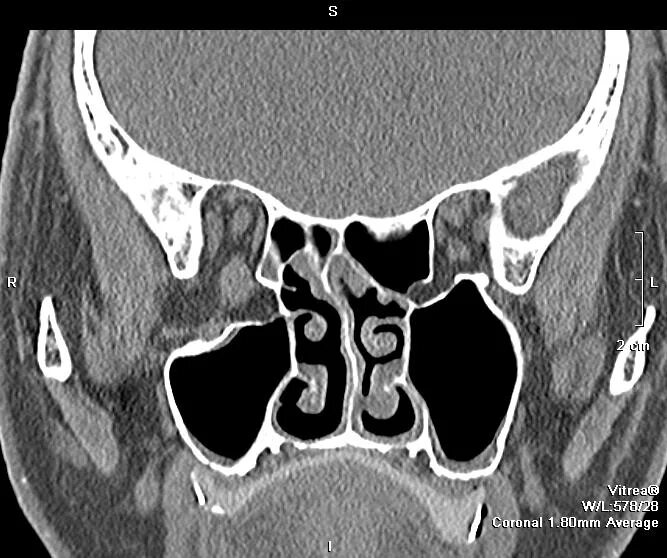

Спинка турецкого седла